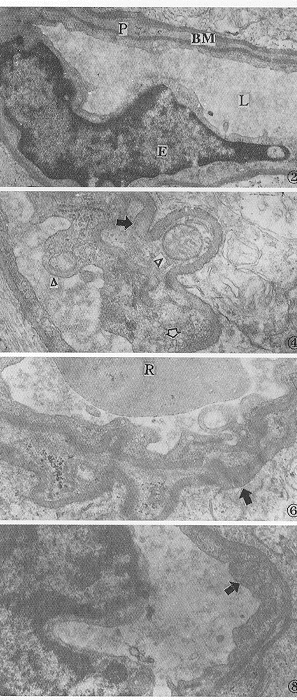

图1 正常组大鼠视网膜膜盘结构清晰,排列规则 ×15000 图2 正常组大鼠视网膜毛细血管。E为内皮细胞核,P为周细胞,BM为基底膜,L为毛细血管管腔 ×6000 图3 造模组大鼠视网膜膜盘排列紊乱,结构溶解破坏 ×15000 图4 造模组大鼠视网膜毛细血管基底膜电子密度不均匀,结节样增厚(黑箭头),胞质内线粒体肿胀(△),有吞饮小泡增多现象(白箭头)×12000 图5 治疗组视网膜膜盘排列较乱,结构模糊 ×10000 图6 治疗组视网膜毛细血管基底膜电子密度不均匀,结节样增厚(黑箭头),胞质内部分线粒体肿胀变性,无吞饮小泡增多现象,R为红细胞 ×15000 图7 预防组视网膜膜盘排列稍乱,结构尚清晰 ×15000 图8 预防组视网膜毛细血管基底膜电子密度不均匀,无结节样增厚现象,线粒体结构基本正常(黑箭头),无吞饮小泡增多现象 ×10000 图9 正常大鼠视网膜血管结构 消化铺片 HE ×100 图10 造模组大鼠视网膜毛细血管排列紊乱,迂曲交叉,有的扭曲成团,管经不规则,粗细不均,出现无细胞毛细血管(黑箭头),可见微血管瘤(*)消化铺片 HE ×200 图11 治疗组大鼠视网膜毛细血管管腔不规则,动静脉排列稍乱,迂曲交叉,但较造模组病变轻,未见无细胞毛细血管。偶可见毛细血管瘤(*)消化铺片 HE ×400 图12 预防组大鼠视网膜毛细血管管腔基本规则,无明显动静脉迂曲交叉现象,无毛细血管瘤和无细胞毛细血管 消化铺片 HE ×200